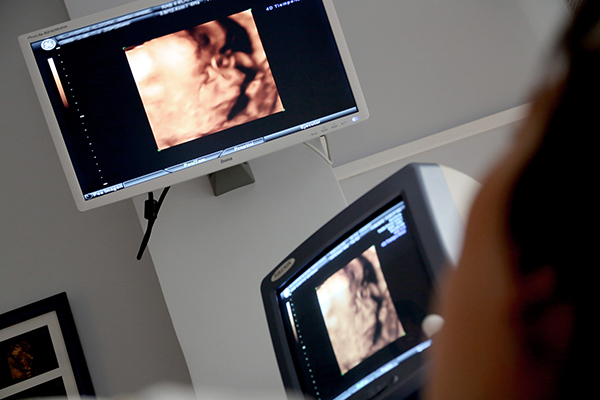

2、超声波检查:超声波大家都知道,它就是我们平常说的B超。B超这项检查其主要目的是为了检查胎儿在宫内的发育情况,但它在看胎儿性别的这个技术上,准确率是被公认的。一般怀孕四个月之后,看性别更准确。